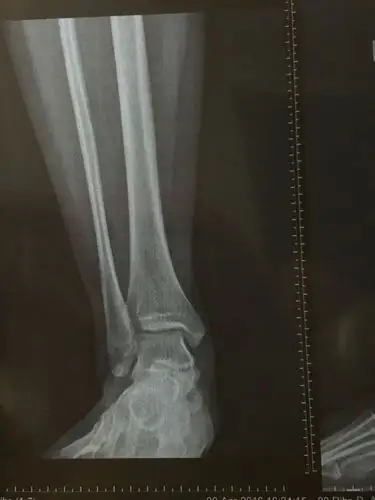

问:踢球扭到脚了,脚内侧骨头突出,医疗专家帮忙看看吧!

右脚骨折手术后这个脚内侧凸出

右脚脚踝内侧有一块骨头突出 很小的时候崴过一次 最近开始偶尔有点疼